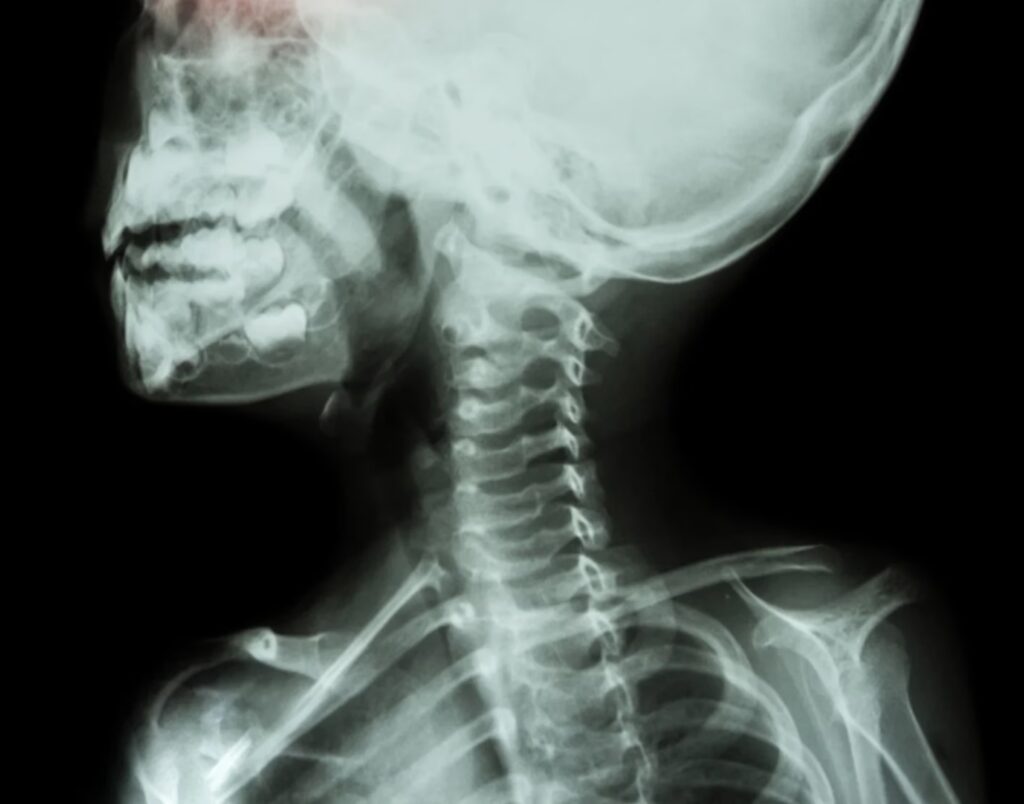

Hvad er en Radiografisk Knogleundersøgelse?

En radiografisk knogleundersøgelse er en diagnostisk billeddannelse, der bruger røntgenstråler til at tage detaljerede billeder af skeletsystemet. I modsætning til et enkelt røntgenbillede, der fokuserer på et specifikt område, undersøger en knogleundersøgelse typisk flere regioner eller endda hele skelettet. Dette gør den særligt nyttig til at identificere udbredte eller systemiske knogleproblemer.

Under proceduren tages en serie røntgenbilleder fra forskellige vinkler for at give et omfattende billede af knoglerne. Testen er ikke-invasiv og generelt smertefri, selvom du måske skal holde bestemte positioner kortvarigt, mens billederne tages. Processen tager typisk mellem 30 og 60 minutter, afhængigt af antallet af billeder, der kræves.

Testen udføres i en radiologisk afdeling eller et billeddiagnostisk center. Afhængigt af det område, der skal undersøges, kan du blive bedt om at ligge ned eller stå under proceduren. En radiograf vil betjene røntgenmaskinen for at tage billeder af dine knogler fra forskellige vinkler. For en helskeletundersøgelse tages der typisk billeder af kraniet, rygsøjlen, bækkenet, ribbenene, arme og ben, hvilket giver et omfattende overblik over dit skeletsystem.